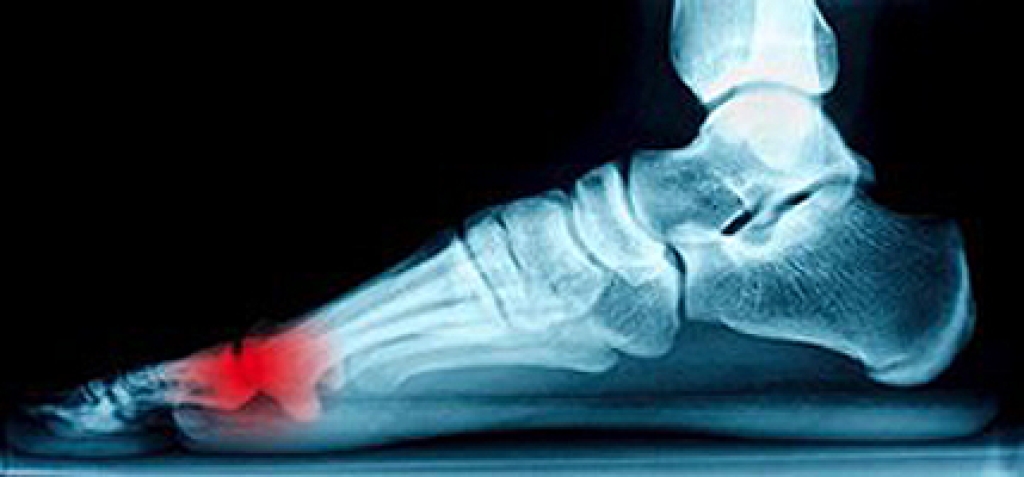

People who pursue careers in podiatric medicine share an interest in helping patients who develop many types of foot conditions. They can properly diagnose and treat uncomfortable ailments including plantar fasciitis, hammer toe, and heel spurs. This is often accomplished by performing physical examinations and X-rays. Additionally, these individuals are able to provide adequate advice on how to take care of diabetic feet, provide necessary medication, and to possibly perform surgery for the correction of deformities that involve the structure of the foot. Those individuals interested in pursuing a career as a podiatrist will earn a DPM degree, and this will typically take 4 years to complete. It may be beneficial to be proficient in developing specific skills, including being able to be detail-oriented, possess critical thinking skills, and to develop compassion. It’s advised to speak with a podiatrist to learn if this is a correct career choice for you.

Someone would seek the care of a podiatrist if they have suffered a foot injury or have common foot ailments such as heal spurs, bunions, arch problems, deformities, ingrown toenails, corns, foot and ankle problems, etc.